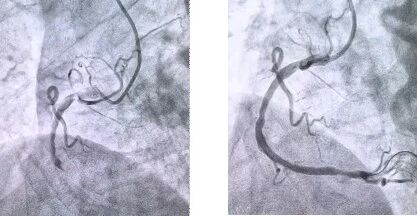

患者抵達醫(yī)院后��,簡化掛號�����、繳費等中間環(huán)節(jié)����,迅速溝通病情���,需要緊急介入治療�����,獲得家屬同意,立即送至導管室���。造影顯示其右冠狀動脈中段完全閉塞����,醫(yī)生迅速實施血栓抽吸,球囊擴張和藥物洗脫支架植入術�����。36 分鐘后��,閉塞血管恢復正常血流�����,吳大爺?shù)难獕?��、心率逐漸平穩(wěn)��,胸痛癥狀明顯緩解��。術后三天����,他便轉(zhuǎn)入普通病房進行康復訓練����,重拾健康生活���。